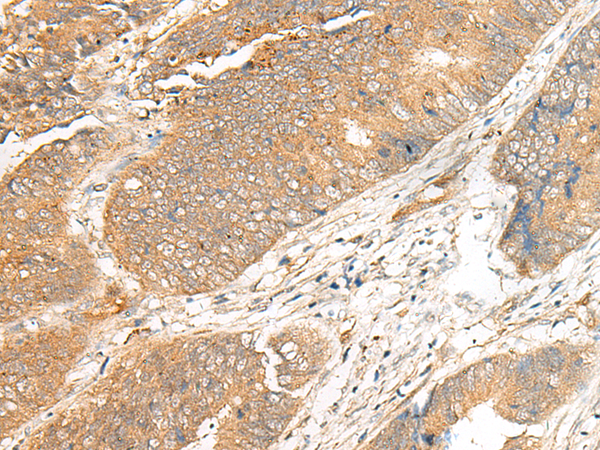

分类: 科研抗体货号: P06610别名: ENA; MENA; NDPP1应用: IHC反应种属: Human, Mouse